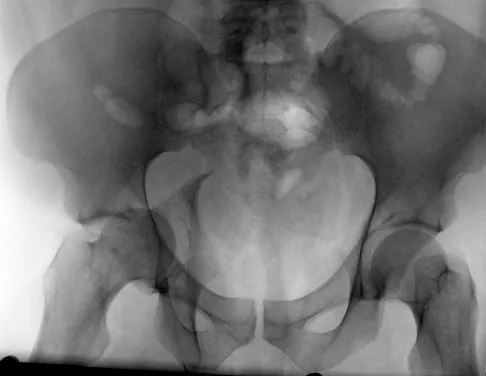

A 32-year-old woman with systemic lupus erythematosus treated with methotrexate and oral corticosteroids reports right groin pain with ambulation and night pain. Examination reveals pain with internal and external rotation and flexion that is limited to 105 degrees because of discomfort. Laboratory studies show a serum WBC of 9.0/mm3 and an erythrocyte sedimentation rate of 35 mm/h. Figures 5a and 5b show AP and lateral radiographs of the right hip. Further evaluation should include

The radiographs show Ficat and Arlet stage 2 osteonecrosis. The femoral head remains round, and there are sclerotic changes in the superolateral quadrant. Patients with systemic lupus erythematosus are at risk for osteonecrosis because of prednisone use and the underlying metabolic changes associated with the condition (hypofibrinolysis and thrombophilia). MRI is the best diagnostic method for detecting osteonecrosis, with a greater than 98% sensitivity and specificity. For this patient, an MRI can assess the contralateral hip for any involvement and can quantify the extent of the lesion. Mont MA, Jones LC, Sotereanos DG, Amstutz HC, Hungerford DS: Understanding and treating osteonecrosis of the femoral head. Instr Course Lect 2000;49:169-185.

- Koval KJ (ed): Orthopaedic Knowledge Update 7. Rosemont , IL, American Academy of Orthopaedic Surgeons, 2002, pp 417-451.